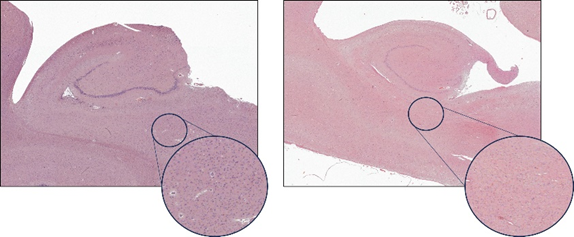

La esclerosis del hipocampo (EH) vista al microscopio. A la izquierda, un hipocampo sin EH (estadio 0) y a la derecha, uno afectado por EH avanzada (estadio IV). Fijándose en el círculo, se puede apreciar la pérdida masiva de neuronas (marcadas en azul) con la EH.

Gracias al estudio liderado por los investigadores Bryan Strange ꟷde la Universidad Politécnica de Madridꟷ y Alberto Rábano ꟷde la Fundación CIENꟷ, así como por las investigadoras Diana Ortega-Cruz y Alicia Uceda-Heras, hoy entendemos mejor la progresión de una de las patologías asociadas a la demencia. En concreto, se trata de la esclerosis del hipocampo, una patología que a día de no puede ser detectada durante la vida de los pacientes. Para entender mejor esta patología, el equipo de investigación evaluó muestras cerebrales de pacientes con demencia pertenecientes a la cohorte Alzheimer de Vallecas – Centro Alzheimer FundaciónReina Sofía (CAV-CAFRS). Este es un proyecto singular, desarrollado por la Fundación CIEN con el apoyo y equipamiento de la Fundación Reina Sofía, que permite estudiar la trayectoria clínica de pacientes con demencia que donan generosamente su cerebro al Banco de Tejidos de la Fundación CIEN. Bajo el microscopio, los investigadores han observado cambios asociados a fases tempranas de la esclerosis del hipocampo y han conseguido establecer un sistema para evaluar su severidad. Este sistema reveló importantes diferencias clínicas, ya que los pacientes en estadios más avanzados de la enfermedad presentaban un peor estado cognitivo. Además, analizando imágenes de resonancia magnética del cerebro de estos pacientes, se pudo comprobar que esta clasificación también reflejaba cambios en la estructura cerebral asociados a esta patología.